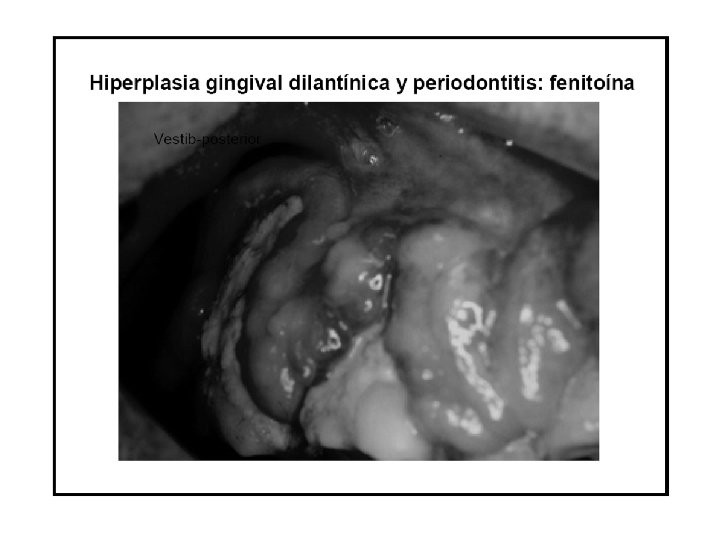

Fenitoína • Reacciones adversas • Aunque mejor tolerado al comienzo del tratamiento que la carbamazepina o el valproato, es más frecuente que produzca efectos secundarios en tratamientos crónicos que con frecuencia pasan inadvertidos, son dosisdependientes suelen observarse con niveles por encima de 20 mg/l y de menor a mayor intensidad son: nistagmo sin diplopía, disartria y alteraciones moderadas de la coordinación, ataxia, visión borrosa y diplopía, náuseas, vómitos, somnolencia, alteraciones mentales, imposibilidad de deambulación.